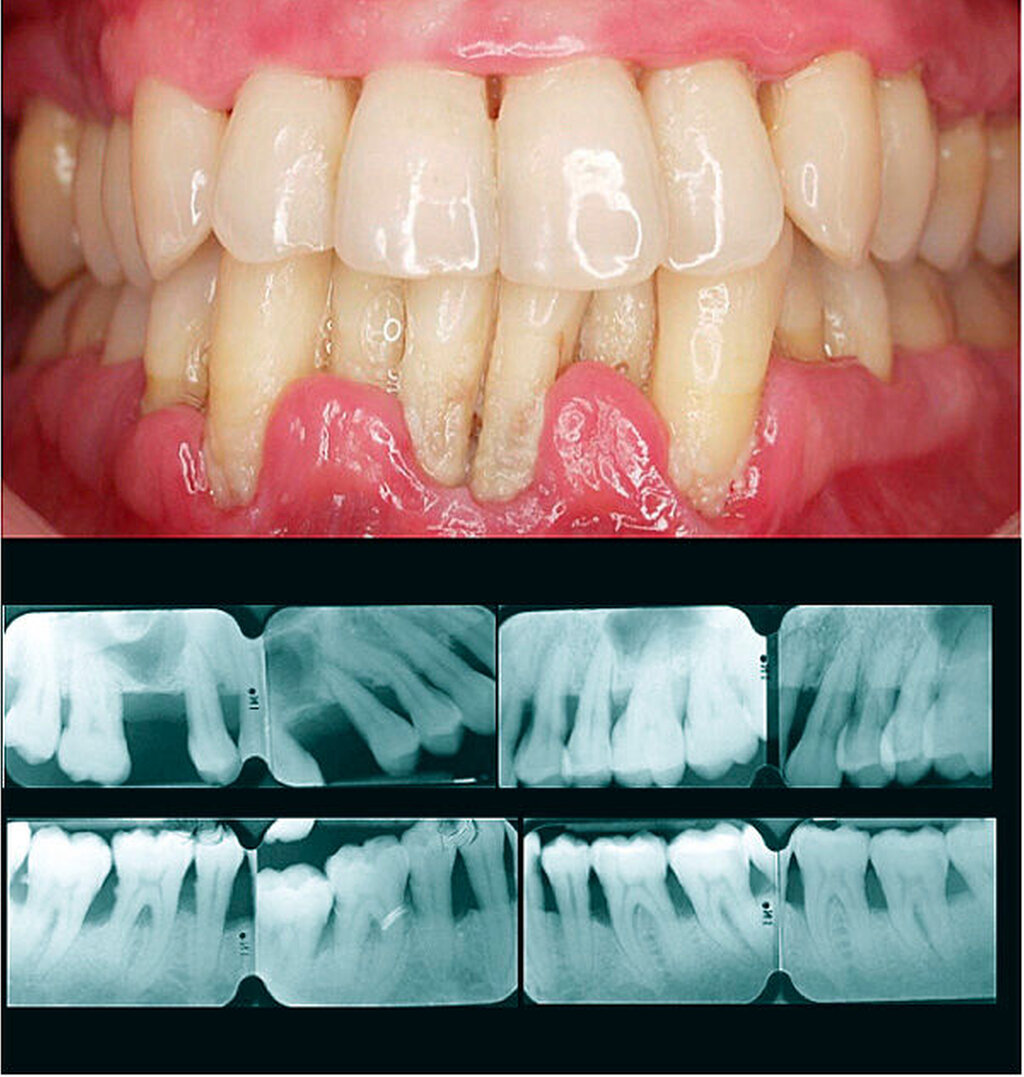

Schritt 3a: Parodontitis-Fall, dessen Stadium festgelegt werden muss

Um das Stadium eines individuellen Parodontitis-Falles festzustellen, sind folgende Informationen erforderlich: vollständiger Röntgenstatus, ein Parodontalstatus und die parodontale Vorgeschichte des Zahnverlusts (periodontal history of tooth loss, PTL). Zuerst bewerten wir das Ausmaß der Erkrankung, indem beurteilt wird, ob CAL/BL weniger als 30 Prozent der Zähne (lokalisiert) oder 30 Prozent und mehr betrifft (generalisiert). Dann definieren wir das Stadium der Erkrankung, indem wir die Schwere (mit CAL, BL und PTL) und Komplexität (durch die Beurteilung von PPD, Furkations- und intraossären Läsionen, Zahnhypermobilität, sekundärem okklusalem Trauma, Bisskollaps, Zahnwanderung, Auffächern oder weniger als zehn okkludierende Zahnpaare) bestimmen.

Schritt 3b: Stadium III und IV versus I und II

Wenn CAL größer als 5 mm ist oder wenn der Knochenabbau das mittlere Drittel der Wurzel oder darüber hinaus an mehr als zwei benachbarten Zähnen erreicht, lautet die Diagnose entweder Stadium III oder Stadium IV. Wenn CAL maximal 5 mm in weniger als zwei Zähnen beträgt, sollten wir nach Furkationsläsionen (Grad II und Grad III) suchen. Wenn diese vorhanden sind, ist die Diagnose entweder Stadium III oder Stadium IV. Wenn nicht vorhanden, sollten wir die PPD überprüfen und wenn diese größer als 5 mm an mehr als zwei benachbarten Zähnen sind, ist die Diagnose entweder Stadium III oder Stadium IV. Wenn die PPD zwischen 3 bis 5 mm liegen, sollten wir PTL bewerten. Wenn es einen parodontal bedingten Zahnverlust (PTL) gibt, ist die Diagnose entweder Stadium III oder Stadium IV. Wenn nicht, ist die Diagnose Stadium I oder Stadium II. Bezüglich der Sondierungstiefen sollte eine klinische Beurteilung erfolgen, um dieses Kriterium für eine Höherstufung von den Stadien I und II auf das Stadium III zu verwenden. So sollte beispielsweise bei Vorhandensein von Pseudotaschen der Parodontitis-Fall im Stadium II verbleiben.

Schritt 3c: Stadien I, II, III und IV

Die Stadien I und II beruhen auf dem Niveau von CAL und BL.

Die Diagnose ist Stadium I, wenn:

(a) BL weniger als 15 Prozent ist und

(b) CAL zwischen 1 und 2 mm liegt.

Die Diagnose ist Stadium II, wenn:

(a) BL zwischen 15 und 33 Prozent liegt und

(b) CAL zwischen 3 und 4 mm liegt.

Die Diagnose ist Stadium III, wenn:

(a) BL in das mittlere Drittel der Wurzel oder darüber hinaus reicht,

(b) CAL 5 mm oder mehr ist,

(c) PTL bis zu vier Zähne beträgt,

(d) zehn oder mehr okkludierende Zahnpaare vorhanden sind und

(e) kein Bisskollaps, keine Zahnwanderungen, keine Auffächerung oder schwerer Kammdefekt vorliegen.

Die Diagnose ist Stadium IV, wenn:

(b) CAL 5 mm oder mehr beträgt,

(c) PTL mehr als vier Zähne ist,

(d) es weniger als zehn okkludierende Zahnpaare gibt oder

(e) wenn es einen Bisskollaps, Zahnwanderung, Auffächerung oder einen schweren Kammdefekt gibt.